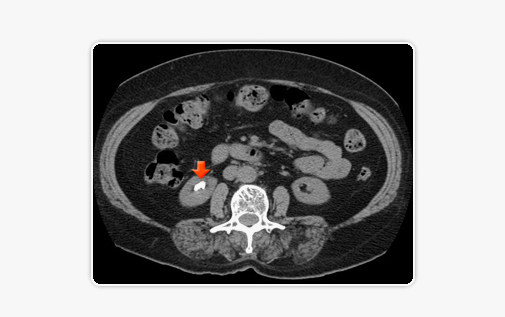

• 복부 전산화 단층촬영(CT) 급성기의 신장 결석과 비뇨기계 결석을 찾는데 크게 도움이 되는 검사입니다. 비교적 크기가 작은 결석도 잘 찾을 수 있으며, 성분과 무관하게 촬영 기계의 해상도에 따라 일정 크기 이상의 모든 결석의 위치와 크기를 확인할 수 있습니다.

신장결석의 CT 소견